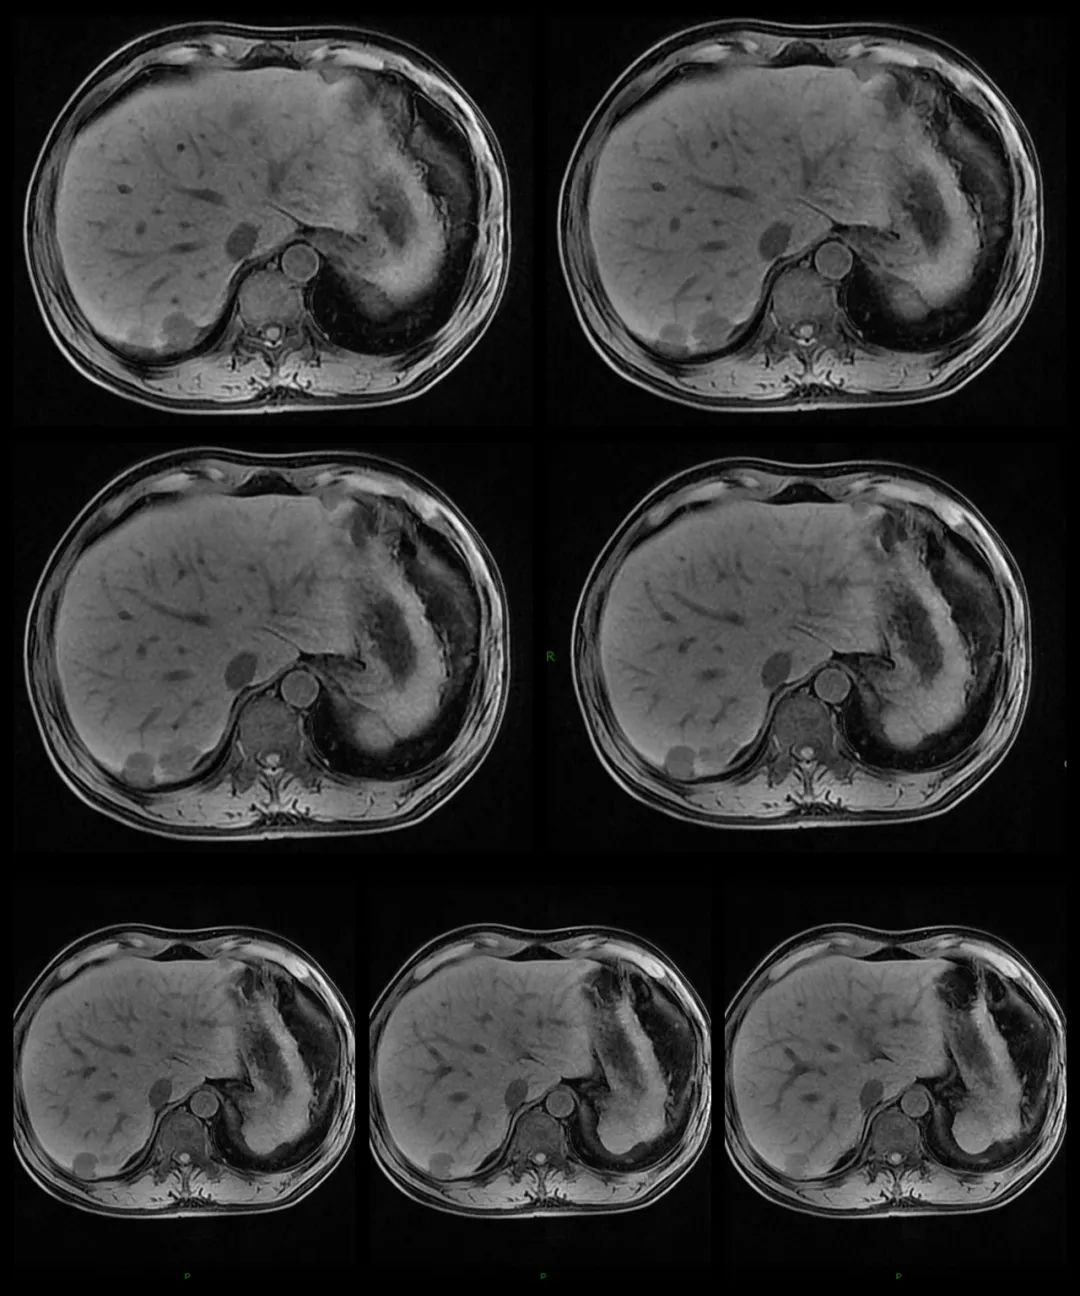

MRI:

MR:多数表现为 T1WI 稍低信号,T2WI 中高信号,与正常脾组织信号相似。增强扫描动脉期、门静脉期和延迟期均为高信号。